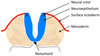

What is the name given to the proliferation of the ectoderm in the dorsal midline?

Neural plate

What happens to the neural plate as it thickens?

- It folds up the sides and eventually the two neural folds fuse to form a tube

- The space in the middle is the neural canal/neural groove

What is the name given to the bunch of cells at the tip of the neural fold that are excluded in the fusion?

Neural crest